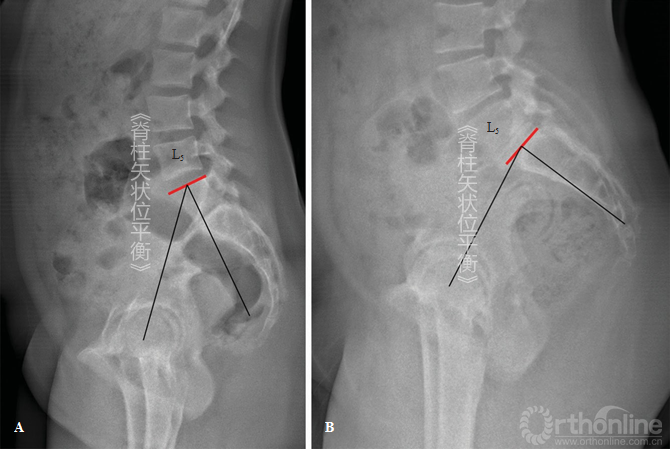

根据这个模型[26,27],腰椎前凸角度被以顶椎为顶点分为上下两个正切圆弧。下弧由骶骨上终板线和通过顶点的水平线形成;上弧是通过顶点的水平线和通过拐点的切线的垂线所确定的角度。一个特殊的几何特性是下弧角度一定和SS角相等。

由于LL在解剖学和功能上的定义可能存在混淆,所以建议LL描述为T12~L1间隙同骶骨上终板之间的弯曲,而骶骨上终板同拐点之间的弯曲作为脊柱远端前凸(distal spinal lordosis,DSL)(图5-10)。在第一种情况下,定义LL只需要一个角度;第二种情况下,需要一个角度和椎体数量去测量角度(图5-10)。

图5-10对比传统腰椎前凸定义和新的脊柱远端前凸角(DSL)

注意前凸弧的长度,黄线为S1上终板,绿线为L1上终板,红色弧线表示DSL。图示的2种情况下,2个DSL存在显著的生物力学差异(左图DSL较小,右侧较大)